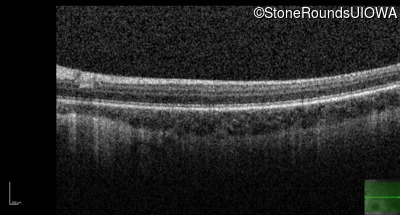

Optical Coherence Tomography - Left - 10/200

Exemplar / OCT Stack